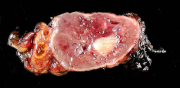

| 09:34, 7 בנובמבר 2012 | תצלוםפאוכרומוציטומה714.png (קובץ) |  |

216 קילו־בייטים | Motyk | 1 | |